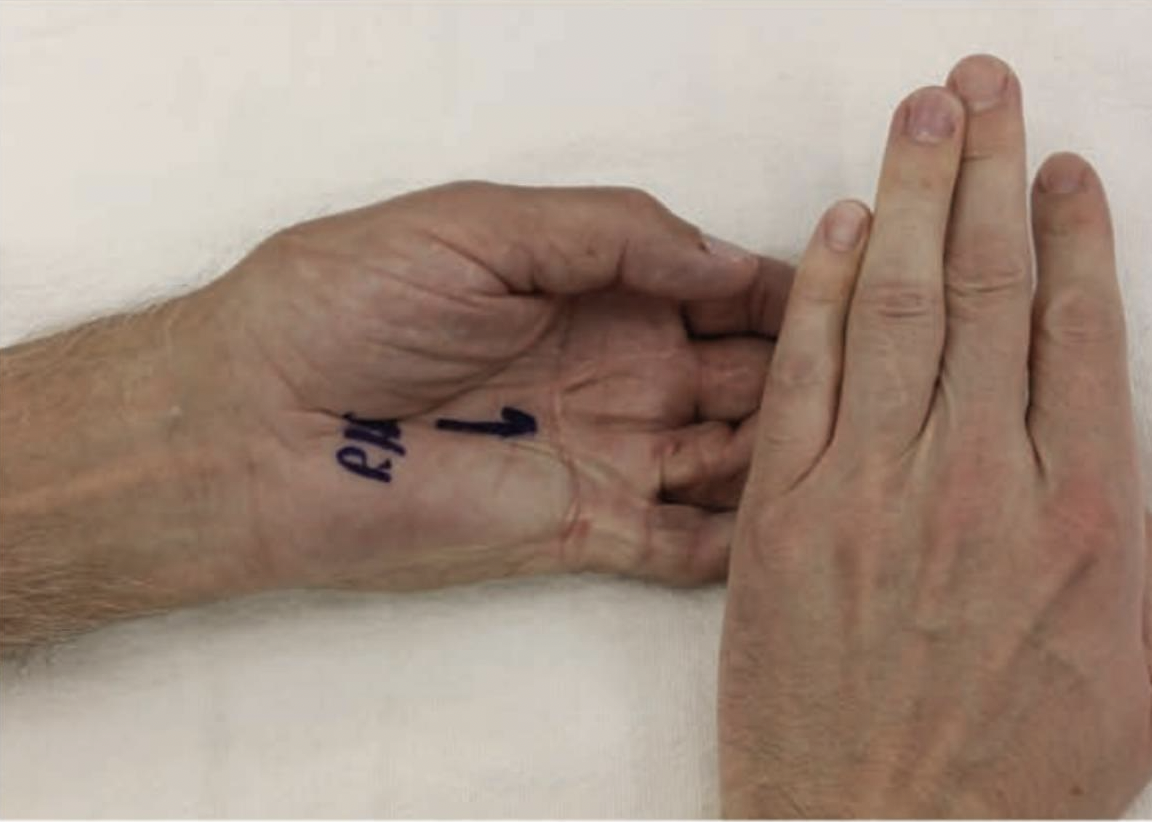

Why Scar Massage Matters After Hand Surgery

After hand surgery or an upper extremity injury, most people expect some pain, swelling, and stiffness. What patients do not always expect is how much a scar can affect movement ...

Why Scar Massage Matters After Hand Surgery

After hand surgery or an upper extremity injury, most people expect some pain, swelling, and stiffness. What patients do not always expect is how much ...

发现扳机指和掌腱膜掌腱膜之间的联系

发现扳机指和掌腱膜挛缩症之间的联系作者:Tayer Roost 参考文献:Yang, Gehring, M.、Bou Zein Eddine, S. 和 Hettinger, P. (2019)。狭窄之间的关联...